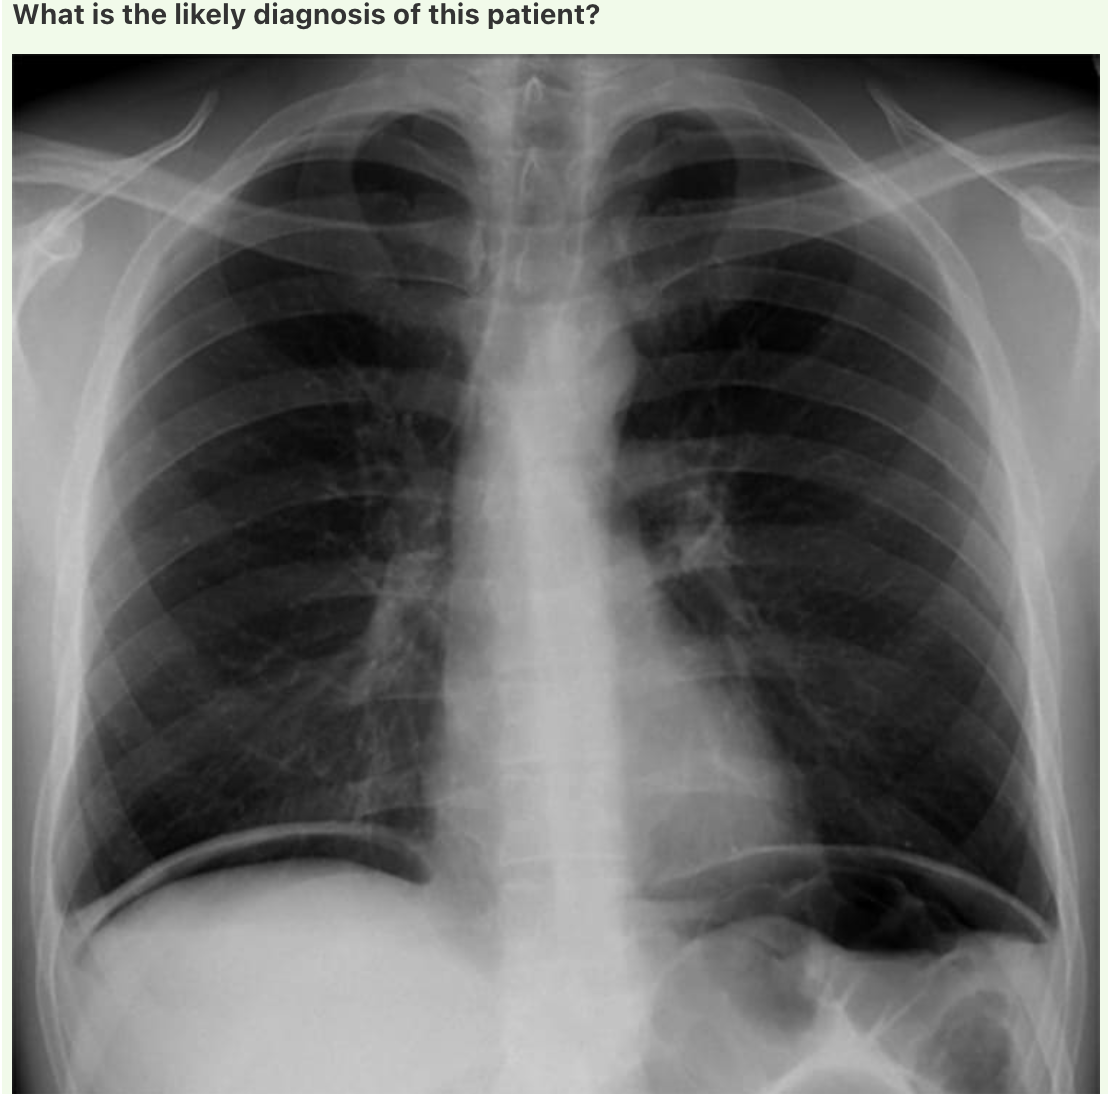

Answer: Chronic Obstructive Pulmonary Disease

In normal subjects, the diaphragm is intersected by the 5th to 7th anterior ribs in the mid-clavicular line - in this patient you can count up to 9 ribs before reaching the diaphragm - > hyperexpanded lungs.

Flattening of the diaphragm is also observed in this x-ray which is a reliable feature of lung hyperexpansion.